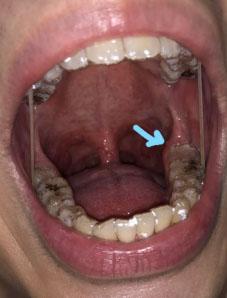

What Is Seen in This Case

The image shows a fresh lower molar extraction site with visible blood and an open socket. This photo was taken about 1–2 hours after the tooth was removed, which explains the presence of blood and raw tissue.

At this very early stage, the socket is still forming a blood clot, which is essential for healing.